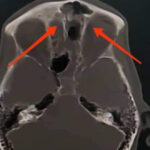

وأوضح مدير الهيئة الدكتور إسكندر عمار في تصريح لمراسلة سانا أنه تم قبول المريض ومتابعته في شعبة الجراحة العصبية، وبعد إجراء الاستقصاءات الشعاعية تبين وجود كسر قاعدة أمامية يسرى على مستوى الجدار الخلفي للجيب الجبهي ويمتد باتجاه الصفيحة الغربالية.

بدوره أوضح رئيس قسم أمراض الرأس والعنق وجراحتها الدكتور محمد خليل اختصاصي الأذنية أنها المرة الأولى التي تجرى فيها عملية نوعية بالتعاون بين الشعبة الأذنية والجراحة التنظيرية وشعبة الجراحة العصبية في المشفى، وذلك بعد تحديد مكان الكسور، ووضع خطة لمعالجتها ليتم التدخل تنظيرياً على منطقة النز والتدخل الخارجي على منطقة الكسر بالجدار الخلفي للصفيحة أو للجيب الجبهي.

وأشار الدكتور خليل إلى أن خطورة استمرار النز تكمن في انتقال السائل الدماغ الشوكي من وسط عقيم الدماغ إلى وسط غير عقيم الأنف، الأمر الذي يحدث التهابات سحايا متكررة تودي بحياة المريض، مضيفاً: إن العمل الجراحي أجري ضمن الإمكانات الموجودة في المشفى، وبخبرات الفريق الجراحي من الأطباء المختصين والمقيمين وأطباء التخدير والكادر التمريضي والفني فيه.